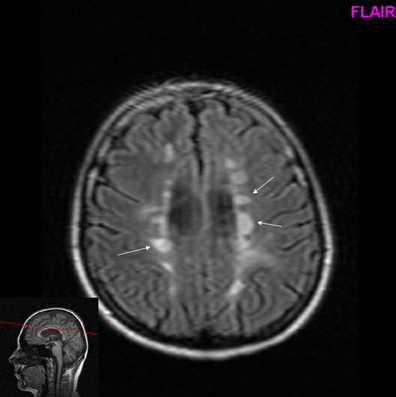

Roztroušená Skleroza / Vite Co Je Roztrousena Skleroza Jake Ma Priznaky A Jak Ji Poznat Jakbytfit Cz - Artróza je degenerativní onemocnění, které vede k omezení pohybu kloubu a jeho poškození.. Mojemedicina.cz slouží pacientům a jejich blízkým, lékařům nebo studentům medicíny. Jul 02, 2021 · multiple sclerosis (ms) is an autoimmune disease that affects the brain and spinal cord (central nervous system). May 11, 2021 · multiple sclerosis is a chronic condition of the central nervous system. Multiple sclerosis, zkráceně ms) je chronické autoimunitní onemocnění, při kterém lidský imunitní systém napadá centrální nervovou soustavu (mozek a míchu), čímž způsobuje demyelinizaci (rozpad myelinových pochev). Sclerosis multiplex), neurodegenerativno oboljenje i autoimuna bolest koja prvenstveno „napada" bijelu masu središnjeg živčanog sustava.